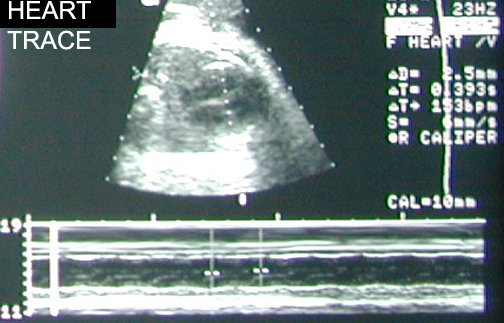

Heart Trace |

|

|